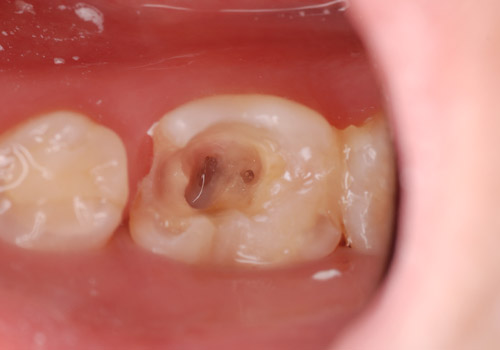

(左:肉眼、右:マイクロ使用)

(上:肉眼、下:マイクロ使用)

徹底的な感染源(虫歯)の除去

まずは感染源となる虫歯を徹底的に除去することから始まります。ここで重要なのはできる限り虫歯の部分だけを削り、健康な歯の部分を保存することです。そのためには非常に精密な手技が必要になりますが、ただでさえ小さい歯の中でそれを肉眼で達成することは難しく、対象物を最大20倍までに拡大することができるマイクロスコープを使うことが必要になります。